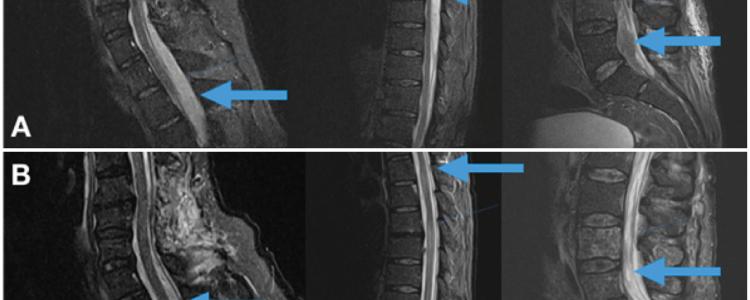

El empiema epidural espinal (EEE) multinivel es una infección rara y grave de la columna vertebral con alta tasa de morbimortalidad. Si bien los abscesos o empiemas de un sector de la columna están bien estudiados, esta patología sorprende por su rareza, reto diagnóstico y terapéutico. Se destaca por ser más frecuente en la edad adulta, en el sexo masculino y se ve asociada a patologías predisponentes.

El agente bacteriológico responsable en la mayoría de los casos es el Staphylococcus aureus. El tratamiento precoz es fundamental y está basado en dos pilares: antibioticoterapia y quirúrgico descompresivo Presentamos dos casos clínicos con afectación multinivel que evolucionaron favorablemente tanto en lo infeccioso como en lo neurológico sin provocar una inestabilidad del raquis y realizamos revisión bibliográfica del tema. Nivel de Evidencia IV; Estudio de Caso-control.